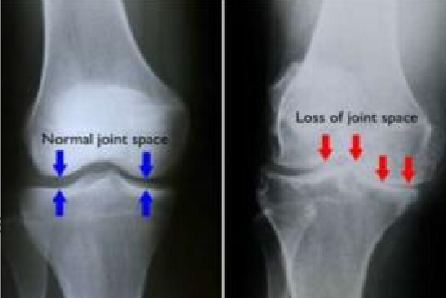

radiology - arthritis

disease of a joint that invariably leads to joint space narrowing & changes to the bones of both sides of the joint

radiology - hypertrophic arthritis

features

subchondral sclerosis

marginal osteophyte production (bone spurs)

subchondral cyst formation

radiology - primary osteoarthritis

most common type of hypertrophic arthritis

typically occur in weight-bearing surfaces of the hip, knee, & distal interphalangeal joints of finger